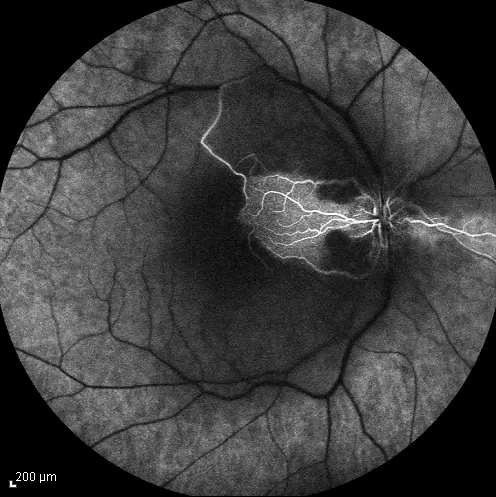

Retinal Photo of diabetic patient

New neovascularization = PDR

Treatment:

- PRP

Pattern of Laser?:

Argon laser PRP (Panretinal Photocoagulation)

Indicated for:

- PDR (Proliferative Diabetic Retinopathy)

- Ischemic central retinal vein occlusion